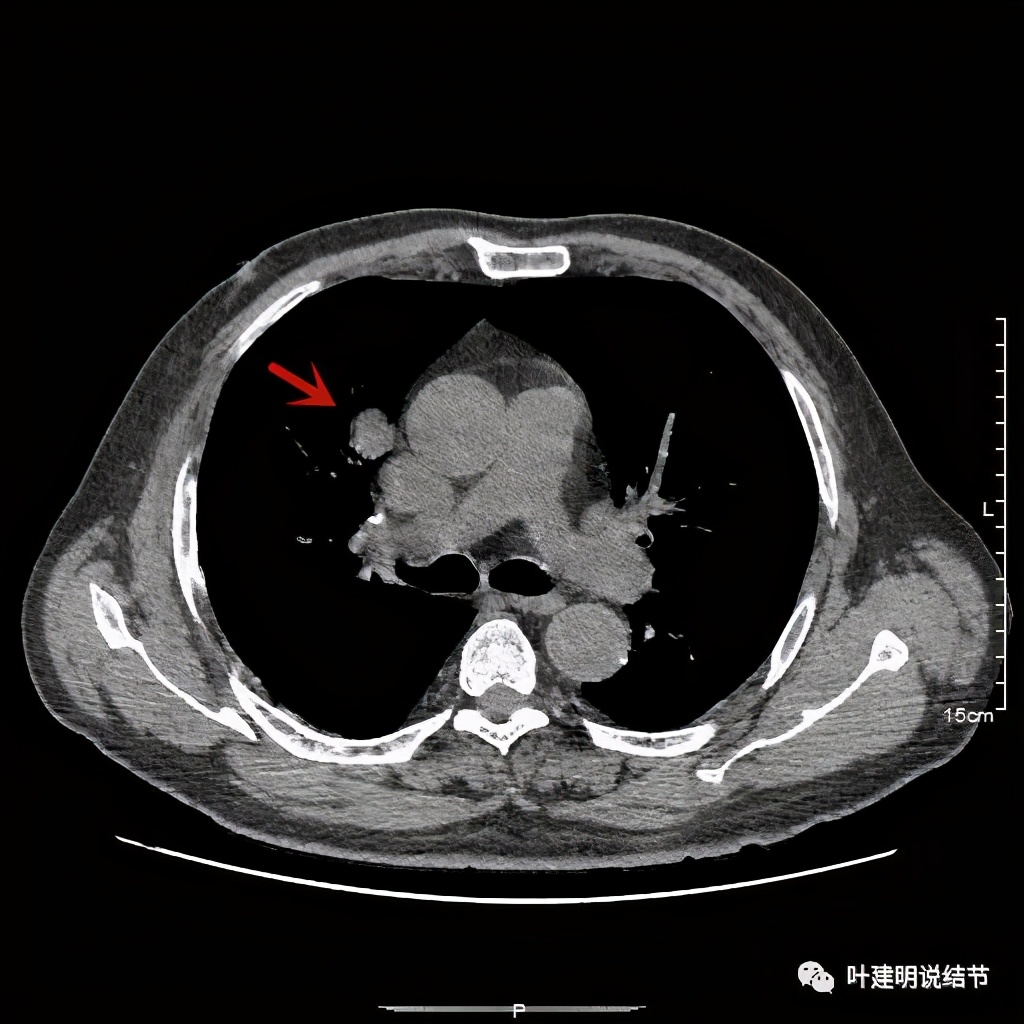

金华的某A,男性,70岁,因检查发现右上肺占位入院,没有临床症状,肿瘤筛查指标正常,血常规与CRP正常。胸部CT检查报告考虑恶性可能:

直径约2.4厘米,密度欠均,血管贴边,增强轻度强化。单从描述看,恶性可能性较大。我们再来看看图像:

可见右上叶占位,我们现在知道了结果以后回头看,发现病灶的边缘在各个层面都是过于光滑(绿色箭头所示)。血管紧贴病灶边走行(桔色箭头所指),是不是有侵犯看不清楚,若是靶扫描加重建可能会更清楚点。支气管感觉也是贴着病灶走,但有的层面是不是截断,也不看的不太清楚。有的层面见局部有点状高密度(蓝色箭头所指),是不是错构瘤的局部钙化呢?若是纵隔窗又是如何?

上图示病灶